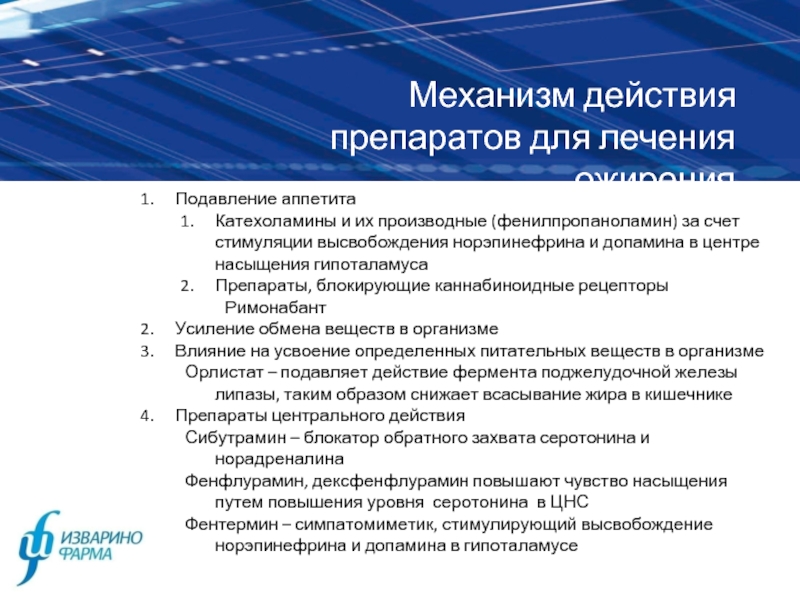

Как работает центр насыщения в гипоталамусе: визуальные иллюстрации